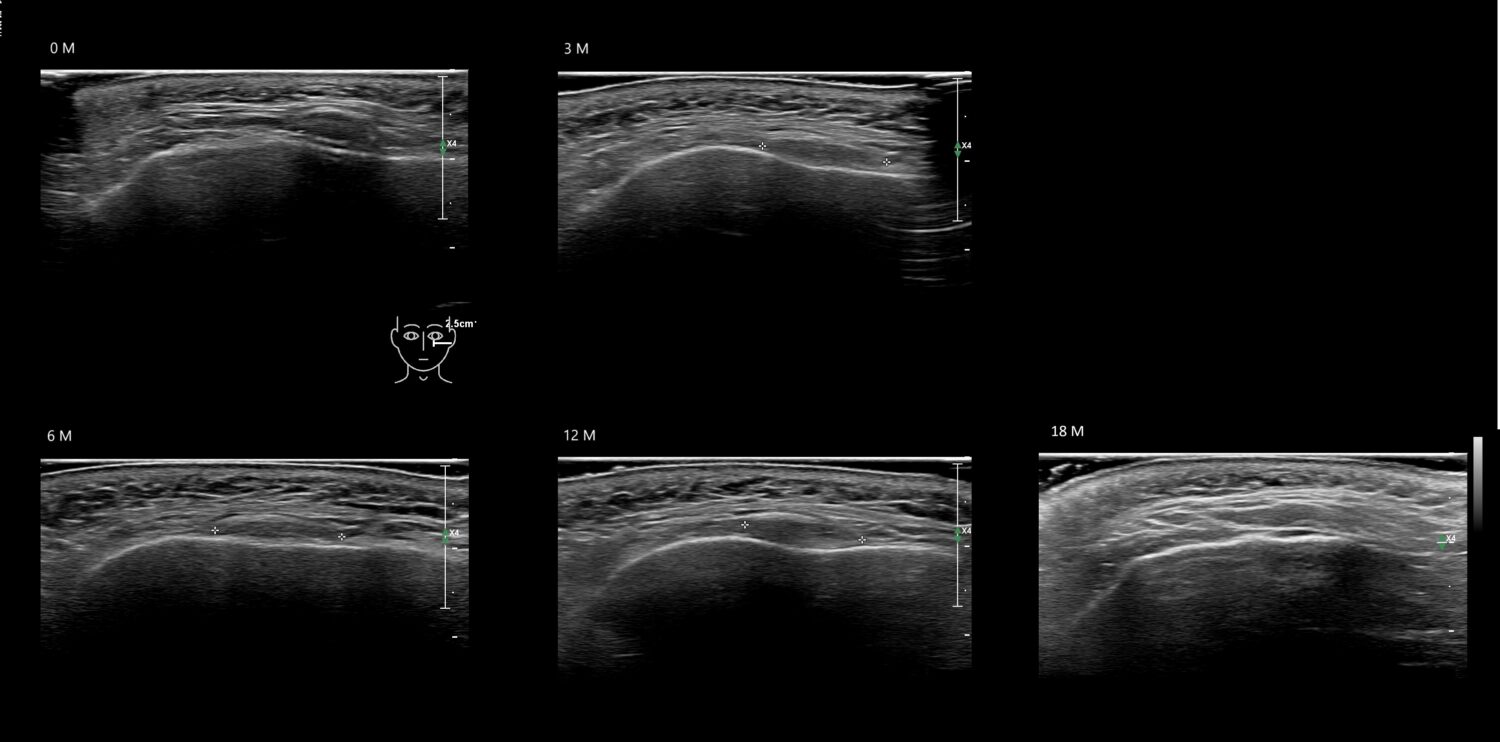

Fillers

Draw in the image on the right where the fillers are located. To check if your answer is correct, please click on the secondary image.